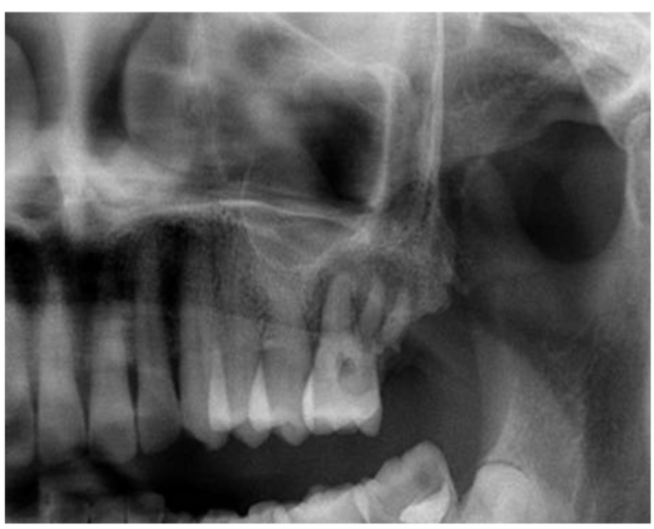

患者,女性,58岁,B7缺失,B6Ⅲ°松动。数码全景片示B6根折,根尖周阴影明显,骨质缺损明显(图17)。

图17 数码全景片(局部)显示B6牙槽骨吸收明显

因为B6根尖和牙周炎症较重,拔牙后没有即刻行拔牙位点保护术。拔牙2个月后,外提升术前CBCT示骨质缺损明显,剩余骨量不足以进行种植体植入(图18)。

图18 同一患者拔牙后2个月CBCT,骨量明显不足A.矢状位;B冠状位;C水平位